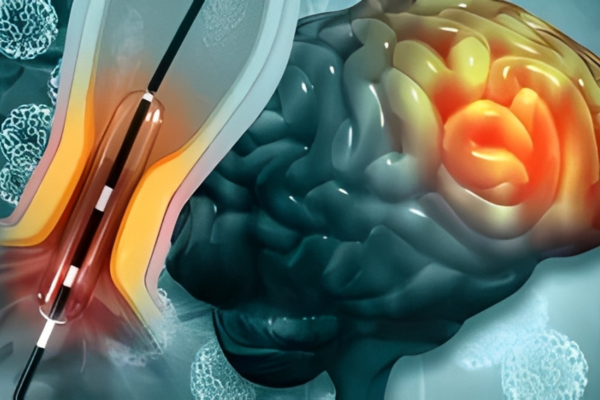

Aneurysm coiling is a minimally invasive procedure used to treat brain aneurysms by preventing rupture. It is performed when weakened blood vessels balloon and pose a serious risk of bleeding.

Using thin catheters, soft coils are placed inside the aneurysm to block blood flow, reduce pressure, and safely prevent future bleeding.